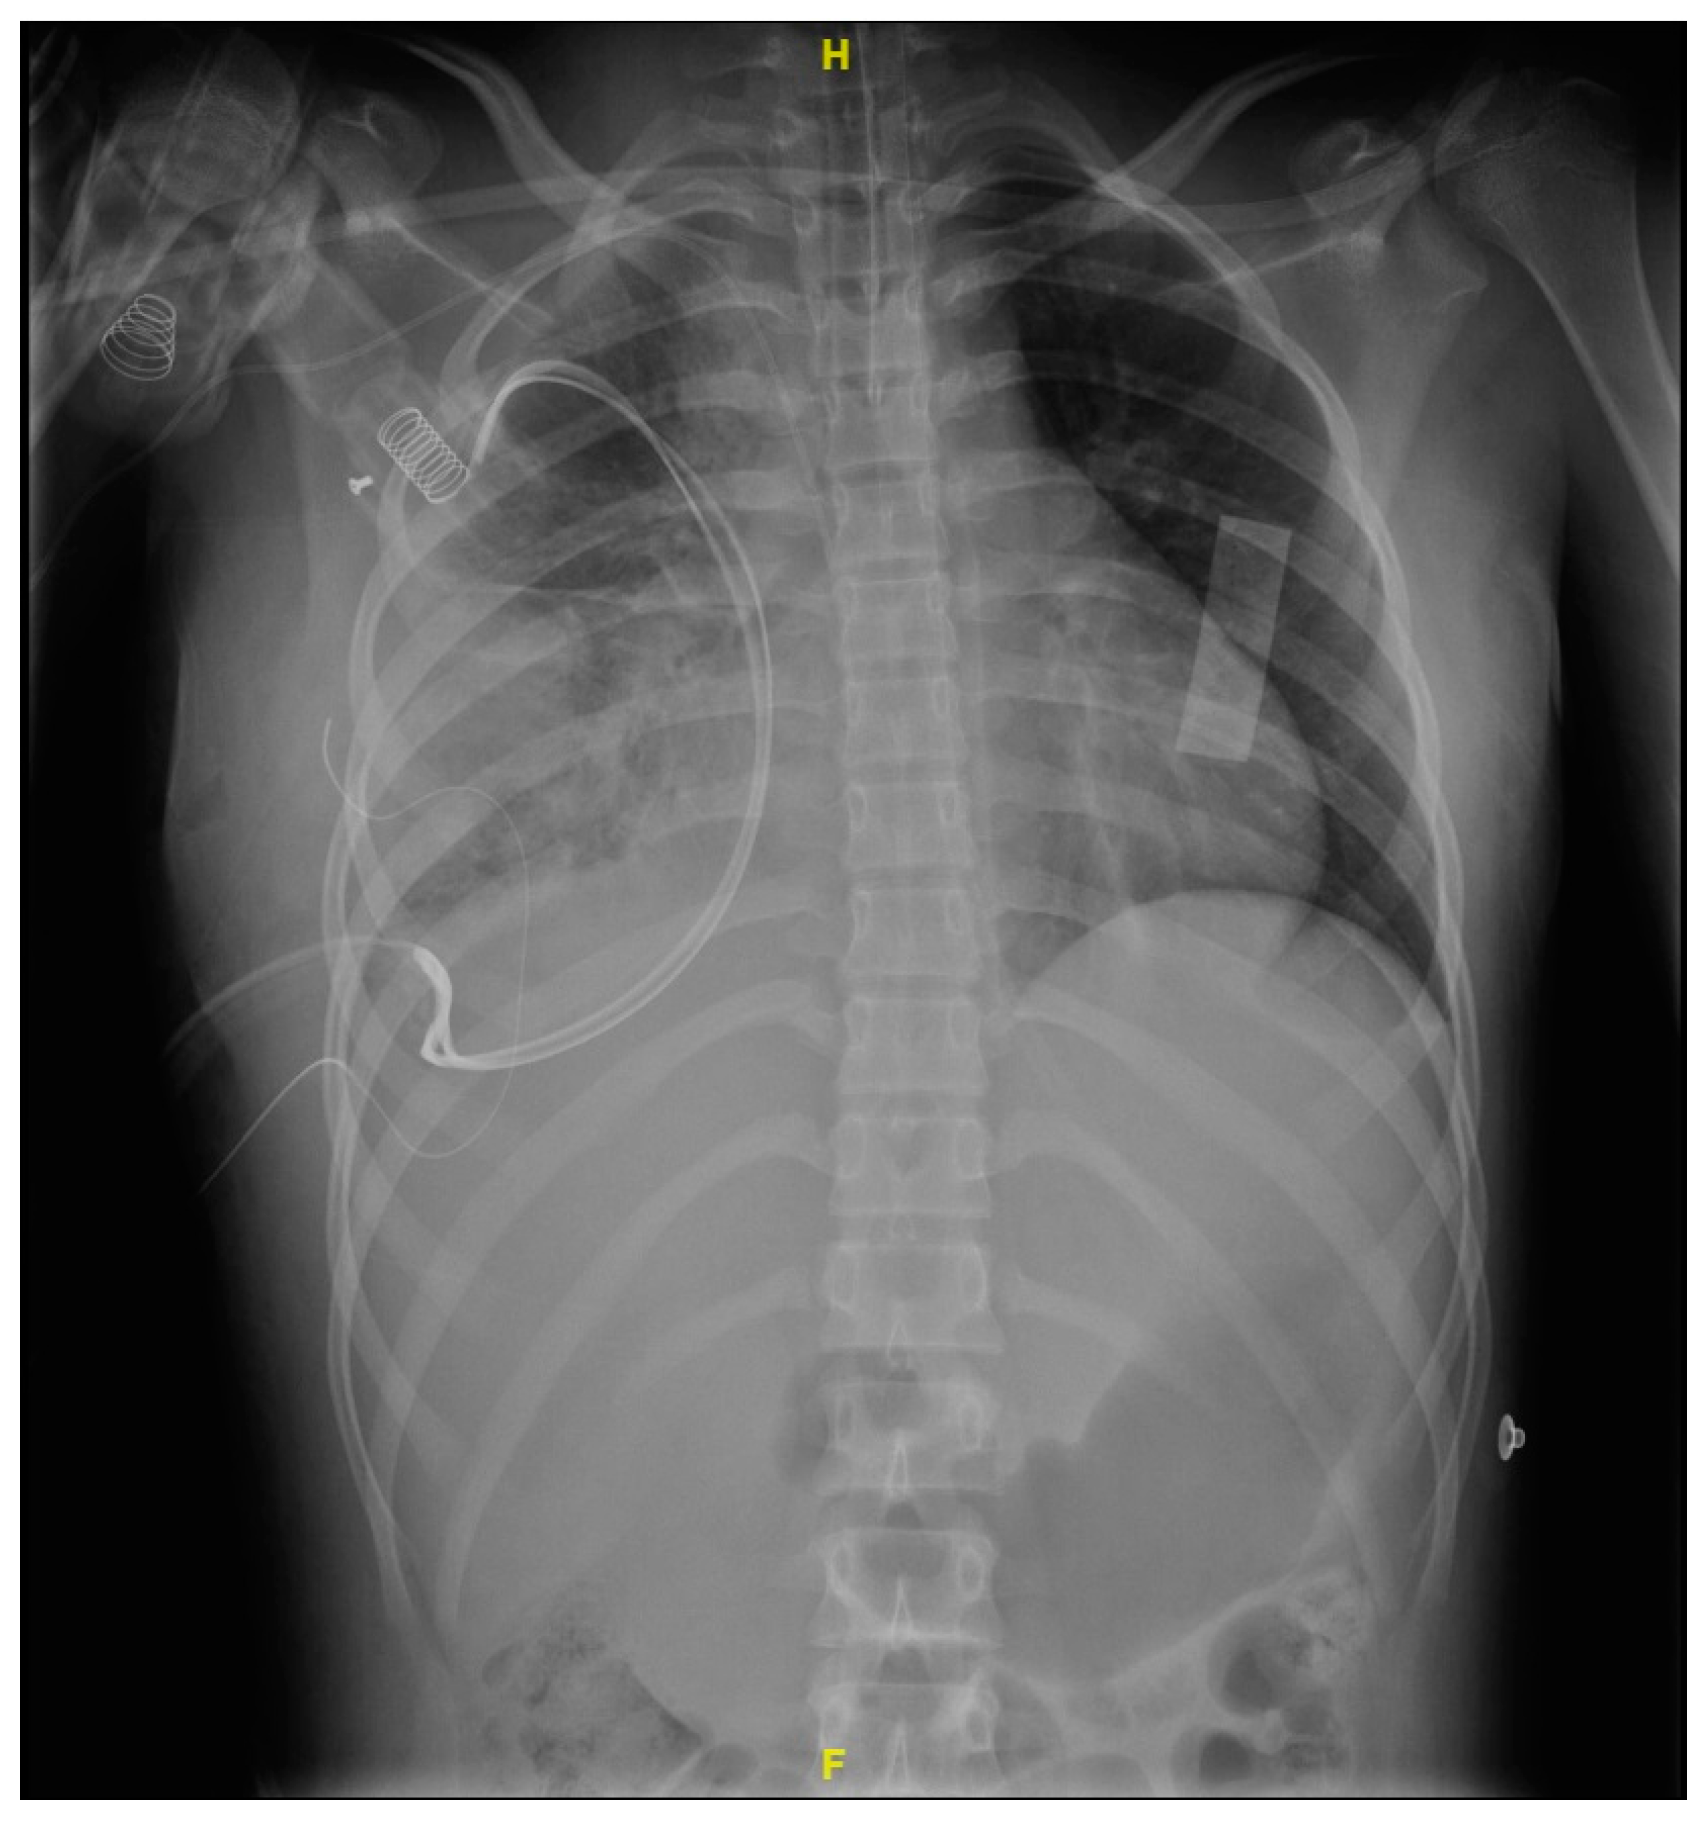

2. Case Presentation